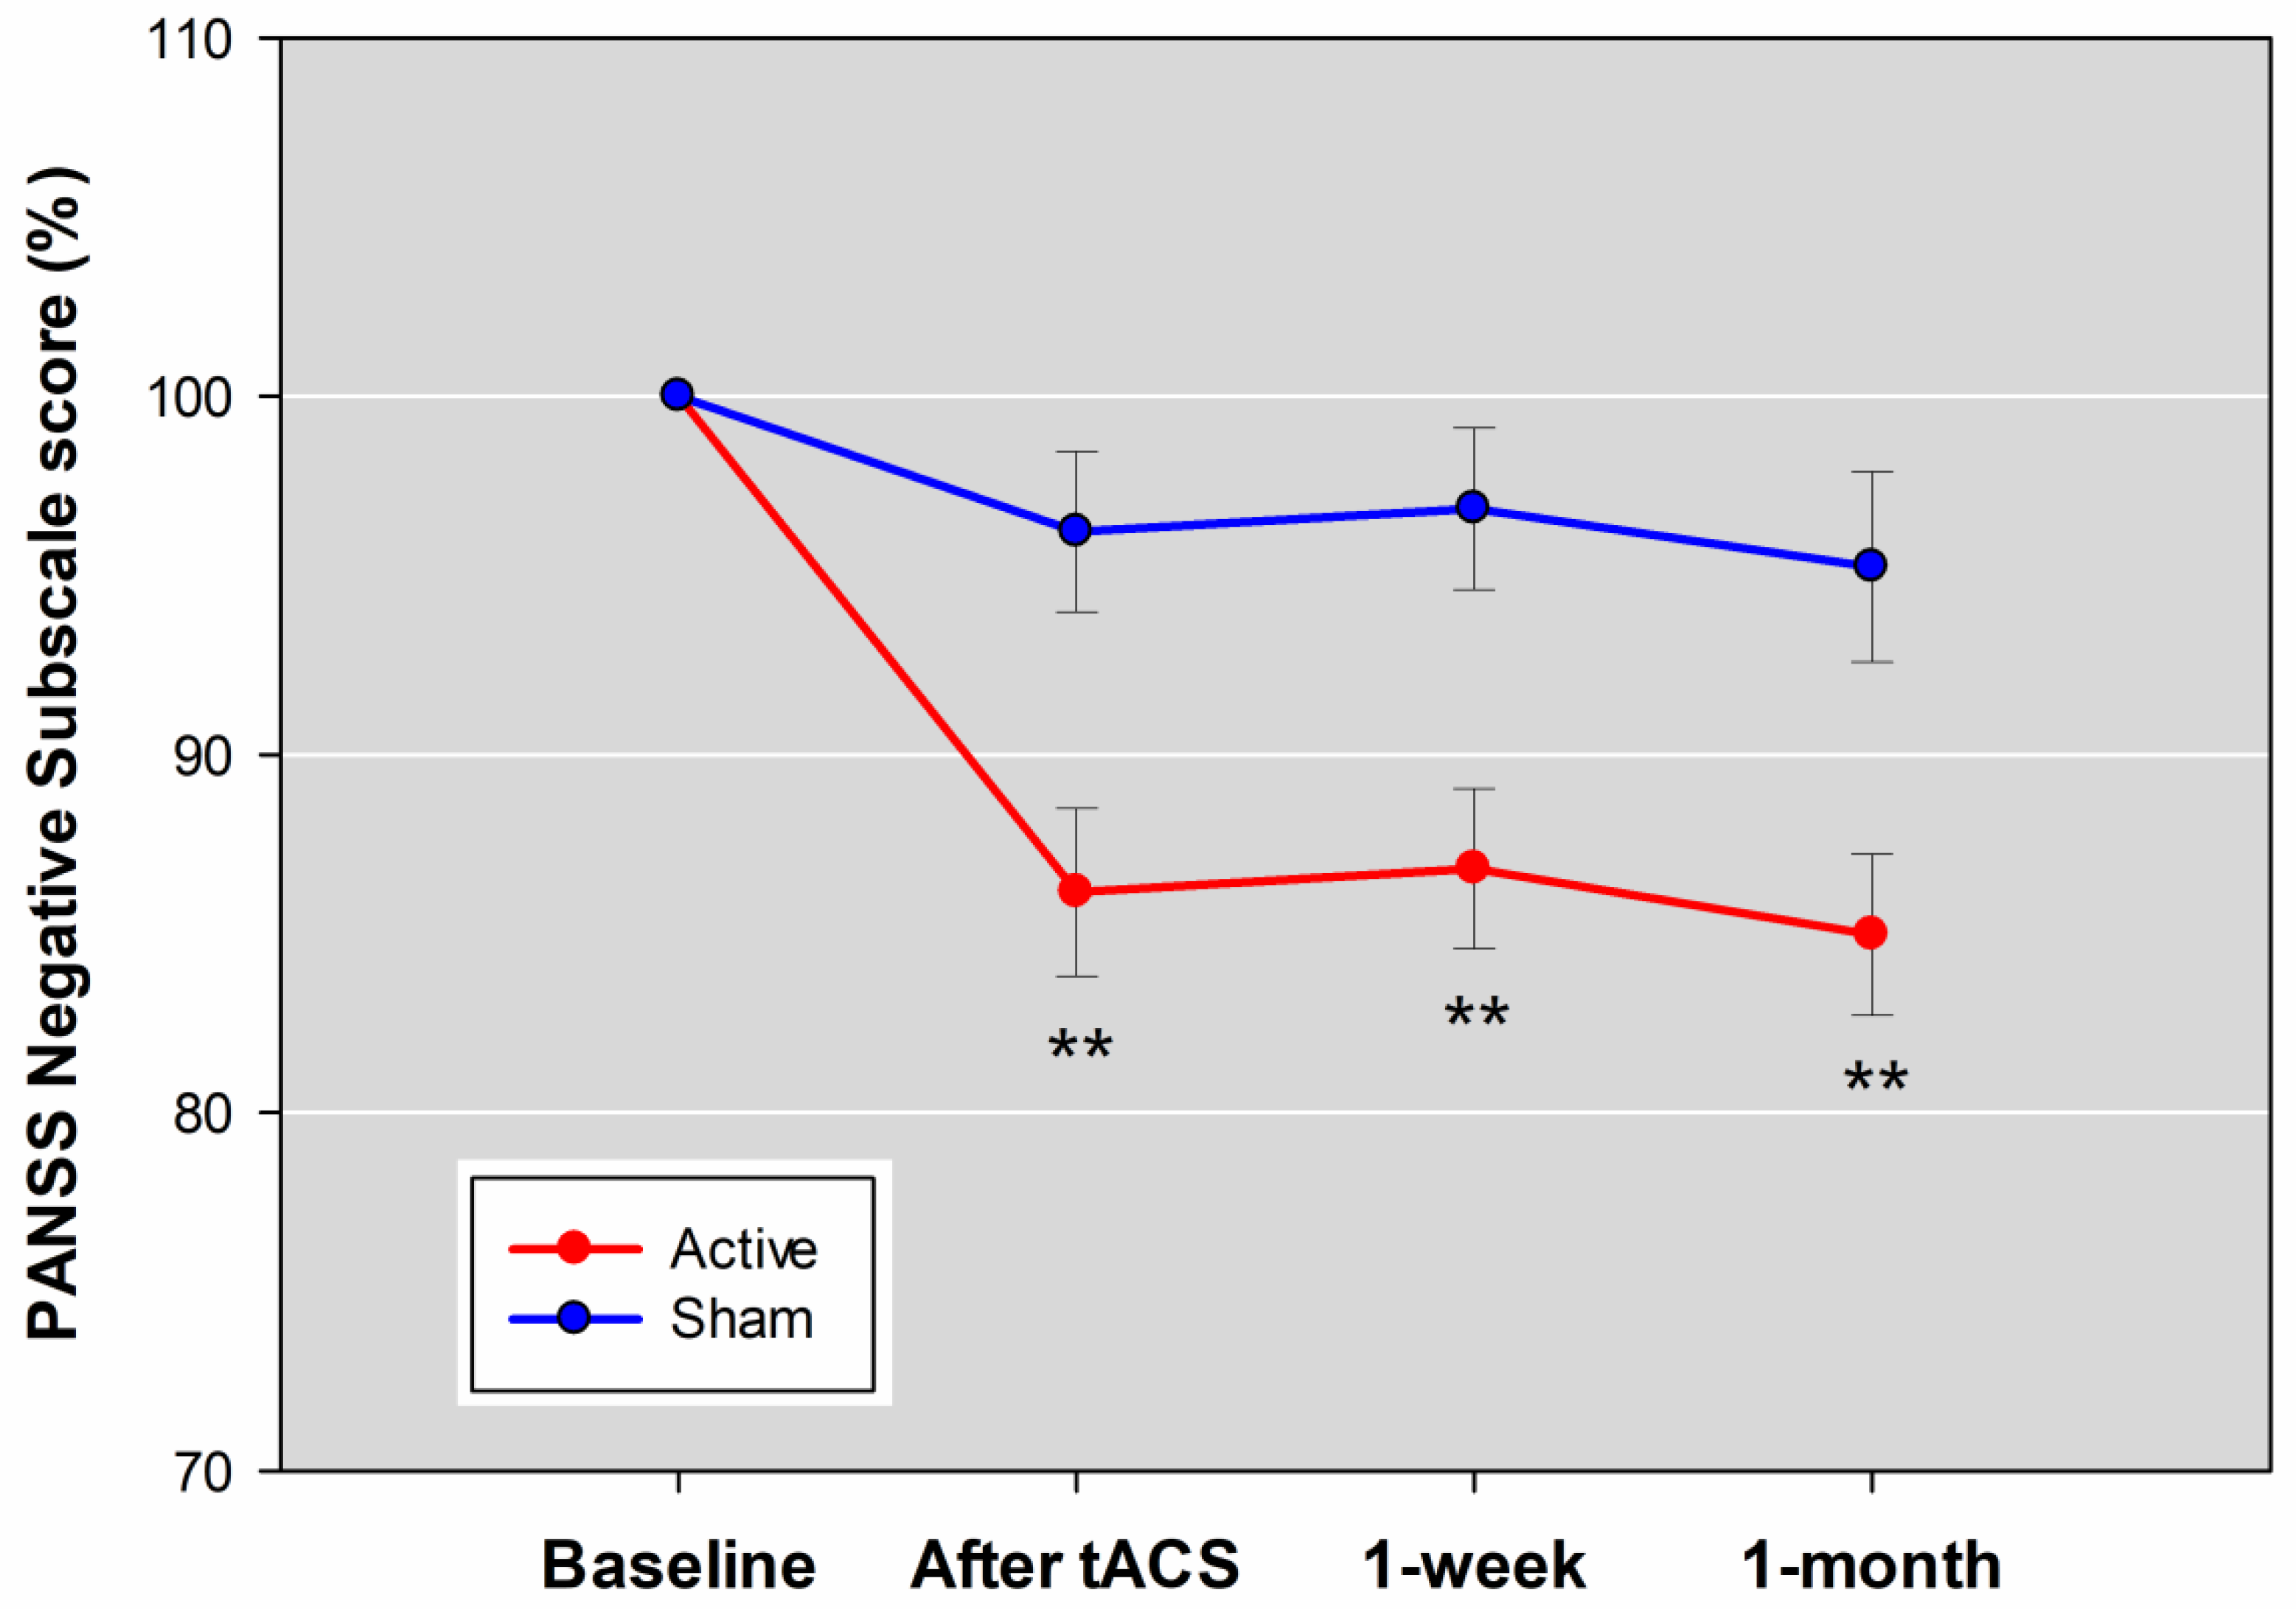

3.2. Primary Outcome

3.3. Adverse Events and Safety